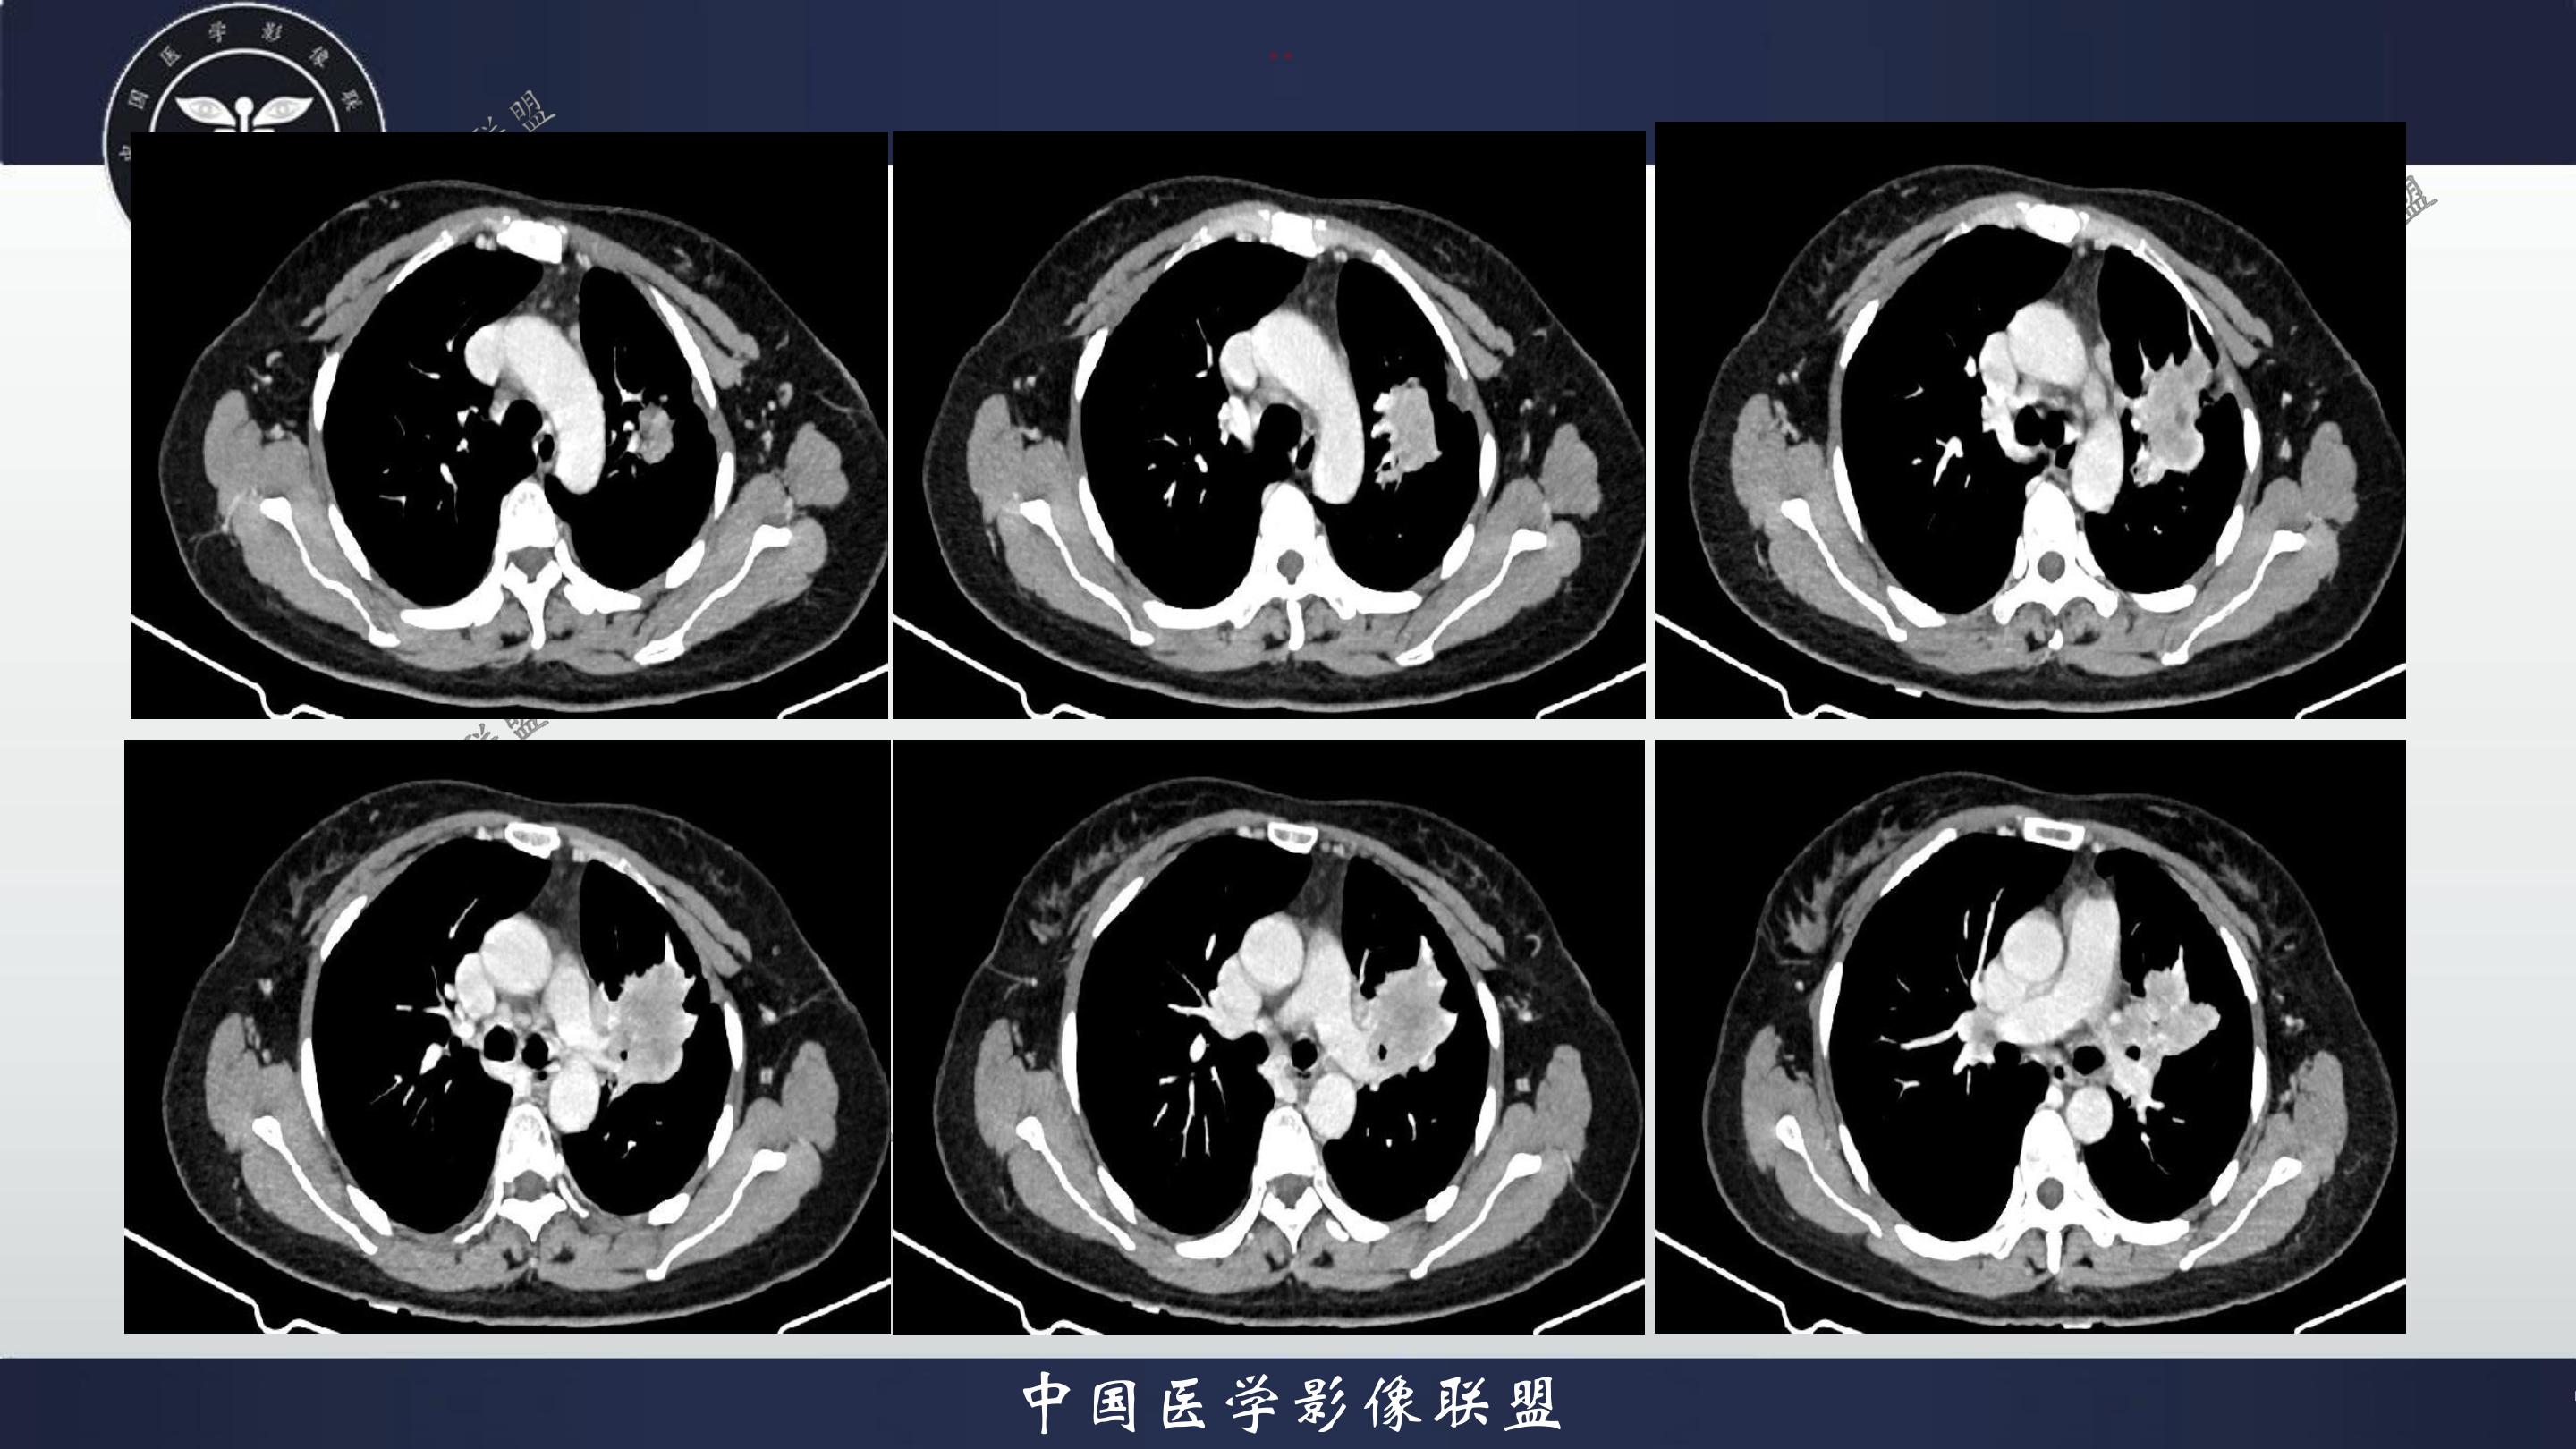

老年女性,咳嗽、咳痰伴痰中带血3月

3月前患者无明显诱因出现咳嗽、咳痰,呈阵发性咳嗽,咳大量黄色脓痰,痰不易咳出,伴痰中带血,量少,具体量不详,伴鼻塞、口干、乏力,活动后感喘息、劳累,休息后缓解,无发热、畏寒,无盗汗,无心慌、胸闷,无腹痛、恶心、呕吐,无头昏、心前区压榨性不适,院外予以输液及口服药物治疗后症状无明显缓解,现为系统诊治就诊我院门诊,门诊以“社区获得性肺炎”收入我科。病来精神、饮食、睡眠尚可,大小便正常,体重无明显变化。

既往有高血压病史10+年,血压最高160/70mmhg,自诉长期口服降压药物治疗,具体药物名称不详;8+年前患者有胆囊结石病史,自诉当时予以手术治疗后好转出院,具体不详;否认“糖尿病、冠心病"等疾病史。否认“肝炎、伤寒、结核”等传染病史;否认已知药物及食物过敏史,否认烟酒史

查体:T:36.8℃P:82次/分,R:20次/分,BP:135/82mmHg,spo2:96%.神清合作,咽稍充血,双侧扁桃体无肿大;双肺呼吸音粗,双肺可闻及少许湿性啰音,未闻及哮鸣音;心界不大,心率82次/分,律齐,心音低钝,各瓣膜听诊区未闻及杂音,腹软,中上腹压痛,无反跳痛及肌卫,肝脾未扪及。双下肢无水肿。

4.辅查:生化报告(2024-11-14 13:06:51)尿素氮或尿素:10.1mmol/L↑,尿酸:342umol/L↑,钾离子:3.16mmol/l↓,尿常规报告(2024-11-14 13:11:41)隐血:+2,凝血报告(2024-11-14 13:16:37)血浆D-二聚体测定:0.62ng/mL↑,生化报告单(2024-11-14 16:14:45)MP滴度(1:40):弱阳性,PCR报告(2024-11-14 16:50:37)人鼻病毒核酸(HRV-RNA)定性:阳性,传染性指标、粪便常规、BNP、心肌特异蛋白、CEA、肝功能、血脂、红细胞沉降率未见明显异常。血气分析回示:PH 7.443 PCO2 28.3mmhg PO2 90.9mmhg HCO3- 19.53mmol/L 氧和指数432.9mmhg;心电图回示:1.窦性心律2.T波改变(Ⅲ倒置、aVF低平)